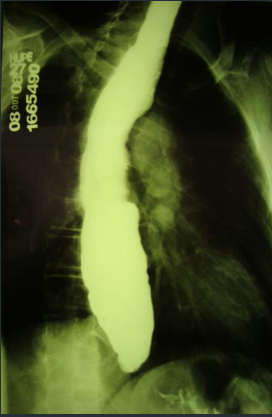

ENUNCIADO DEMOSTRA FRATURA PÉLVICA , COM DESLOCAMENTO DA PRÓSTATA AO TOQUE.

1.CONDUTA –> FIXAÇÃO EXTERNA DA PELVE .

O EXAME DEMONSTRADO É :

1.URETROCISTOGRAFIA RETRÓGRADA ( CONSIDERAR CONTEXTO DO TRAUMA )

2.DEMONSTRA LESÃO DE URETRA .

LEMBRANDO QUE NESSE CASO , NÃO PODEMOS FAZER CATETERIZAÇÃO VESICAL .

* SE A URETROCISTOGRAFIA ESTIVESSE NORMAL DEVERÍAMOS REALIZAR CISTOGRAFIA.